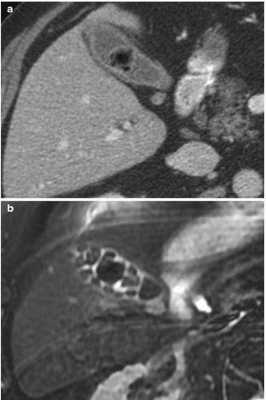

Конкременты в желчном пузыре при КТ

Вид конкрементов у одного и того же пациента в желчном пузыре при КТ (а) и МРТ (b)

КТ обнаруживает примерно 75% камней в желчном пузыре и протоках. Чувствительность способа зависит от состава конкрементов.

Результаты компьютерного сканирования не позволяют увидеть мягкие камни, но плотные конкременты визуализируются на томограммах хорошо.